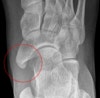

Foot DP, lateral, oblique view를 촬영합니다.

X-ray : 부주상골 증후군(Accessory navicular)